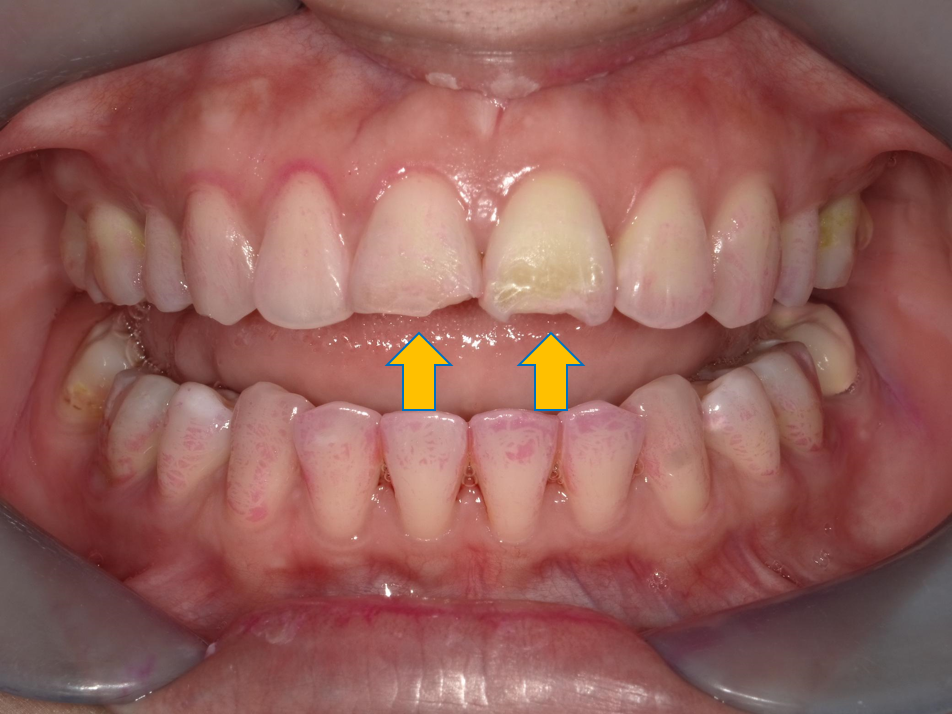

案例 1 術前(Before)

門牙部分缺損磨耗,造成咬合問題